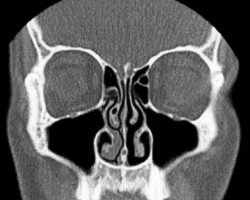

Носовой (назальный) цикл (НЦ) — физиологический феномен[1][2][3], заключающийся в циклическом изменении степени набухания пещеристых тел слизистой оболочки обеих половин полости носа. Наблюдается у людей и некоторых других животных.

Носовой цикл — периодические изменения сопротивления слизистой оболочки правой и левой половин носа в ответ на проходящую через них воздушную струю[1].

Носовой цикл упоминается в древнеиндийской йогической литературе о пранаяме[4]. В современной западной литературе был впервые описан немецким врачом Рихардом Кайзером в 1895 году[5]. Согласно Кайзеру, носовой цикл состоит из двух фаз: рабочей (вазоконстрикции) и фазы отдыха (вазодилатации)[6]. Таким образом, правая и левая ноздри пропускают воздух неравномерно, одна из них лучше, а другая — хуже[7]. Считается, что носовой цикл способствует восстановлению «отдыхающей» слизистой оболочки после микротравм, обеспечивает лучшую элиминации микроорганизмов, аллергических агентов и других мельчайших частиц. Продолжительность одного цикла у взрослого человека в среднем составляет от 2,5 до 3,3 часов, варьируясь от 50 минут до 7,3 часов, у детей — в среднем от 42 минут до 1,9 часов, варьируясь от 15 минут до 3,5 часов[1]. Реснички на рабочей стороне приостанавливают свою подвижность до тех пор, пока эта сторона не снимет набухание. Происходит увлажнение поступающего воздуха в одной из оболочек перед поступлением в лёгкие, что является одной из важнейших функций носа[8]. Работа цикла может нарушиться под влиянием токсических веществ, в том числе табачного дыма, интраназальных инсталляциях некоторых лекарственных средств, или патологических процессов в полости носа и околоносовых пазухах. Цикл нарушается либо исчезает полностью, что мешает нормальному функционированию слизистой, а также может привести к нарушению работы других органов[2].

При болезни, когда к носу приливает больше крови, увеличивается отёк в слизистой, прибавляясь к уже набухшему в ходе носового цикла. Поэтому при полной заложенности носа чувствуется, что одна из ноздрей заложена сильнее[9].